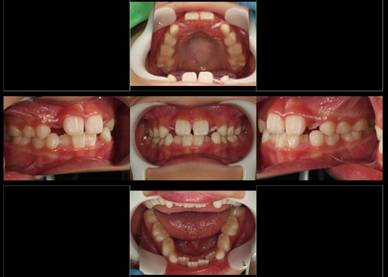

インビザラインによる矯正症例2 22歳女性

治療開始時。正中離開と過蓋咬合がありました

治療途中 5か月後

治療終了 治療開始後7か月